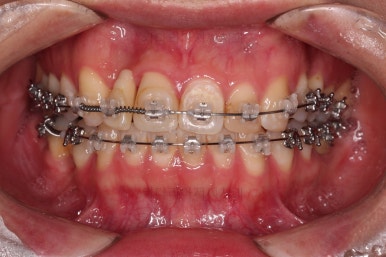

임플란트 완료시 모습인데요.

임플란트 식립부터 완료까지 시간이 걸리다보니 최종 종료까지는 총 19개월이 걸렸습니다.

교합도 잘 맞고 임플란트도 잘 완성되었네요.

매복치아도 손상 없이 잘 배열이 되었고, 교합도 좋게 마무리 되었습니다.